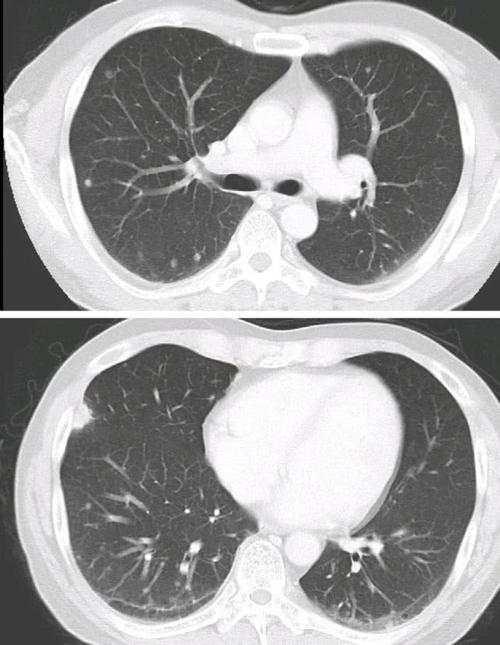

肺部孤立性病灶,直径>3cm的叫肿块(团块),直径介于1-3cm的叫结节,而

肺磨玻璃结节的ct诊断